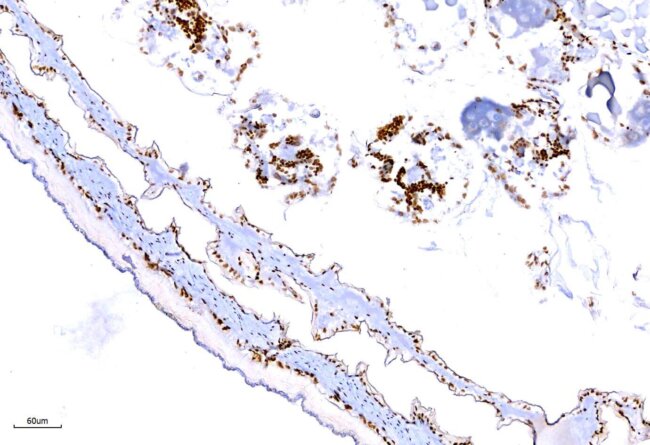

原位雜合試驗(In situ hybridization, ISH)